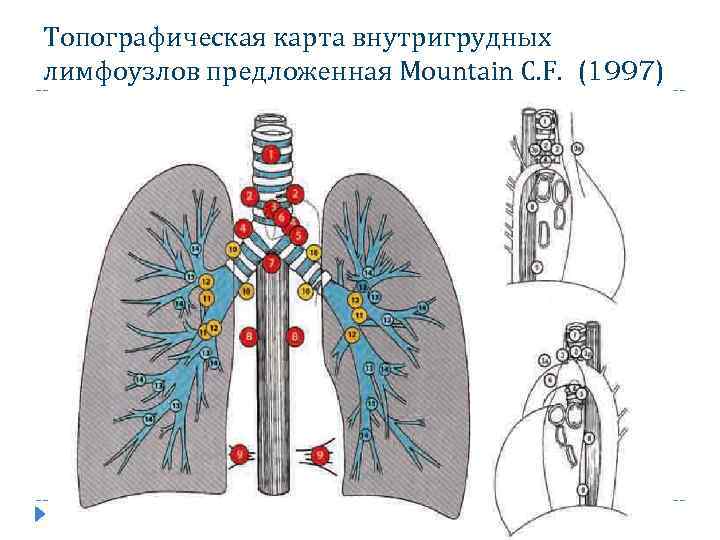

Топографическая карта внутригрудных лимфоузлов предложенная Mountain С. F. (1997)

Топографическая карта внутригрудных лимфоузлов предложенная Mountain С. F. (1997)

Классификация лимфоузлов средостения 1. Верхние медиастинальные 2. Верхние паратрахеальны. 3. Преваскулярные и ретротрахеальные 4. Ретротрахеальные 5. Нижние паратрахеальные 6. Подаортальные ( аортолегочное окно ) 7. Парааортальные лимфоузлы 8. Субкаринальные 9. Параэзофагеальные 10. Легочной связки 11. Корневые 12. Междолевые 13. Долевые 14. Сегментарные 15. Субсегментарные.

Классификация лимфоузлов средостения 1. Верхние медиастинальные 2. Верхние паратрахеальны. 3. Преваскулярные и ретротрахеальные 4. Ретротрахеальные 5. Нижние паратрахеальные 6. Подаортальные ( аортолегочное окно ) 7. Парааортальные лимфоузлы 8. Субкаринальные 9. Параэзофагеальные 10. Легочной связки 11. Корневые 12. Междолевые 13. Долевые 14. Сегментарные 15. Субсегментарные.